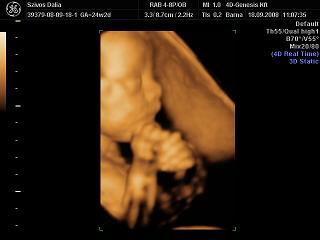

Sajnos nem bírtam ki a 30.-adik hétig,látni akartam Tomi babát azonnal.A genesisben voltunk,majdnem 3/4 órát moziztunk,azt mondták nagy baba,hát nem kizárt,az apja 193cm.

Liuska: Tomika gyönyörűséges! Az a kis nózi! El is hiszem, hogy nem bírtad ki a 30.hétig, én is kérdeztem a dokimat, hogyha meglesz végre valahára a 4D majdnem a 26.héten, ás 32 hetesen megyek a következőUH-ra kb, közte lehet-e egyet mozizni? :oops: Mosolygott, hogy persze, mondjuk hetente nem lenne értelme, de az belefér, hogy a 29.hét környékén... Asszem, bejelentkezem :D

Liuska, de gyonyoru kep, nagyon nagyon tisztan latszik, es tenyleg fantasztikus a nozija, azt hallottam ilyenkor mar az nem valtozik.

Gyönyörű kispasitok van! :) Olyan formás kis fejecskéje és nózija van :)

Liuska, gyönyörű Tomika. Nagyon jól sikerült ez a kép!